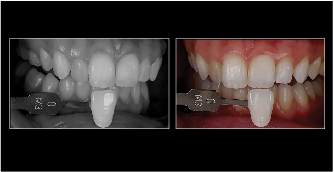

Fig 15. Smartphone dental photography can also be used in laboratory shade communication. In these images taken using MDP, the photo on the left shows value selection, while the one on the right shows chroma/hue selection.

Figure 15